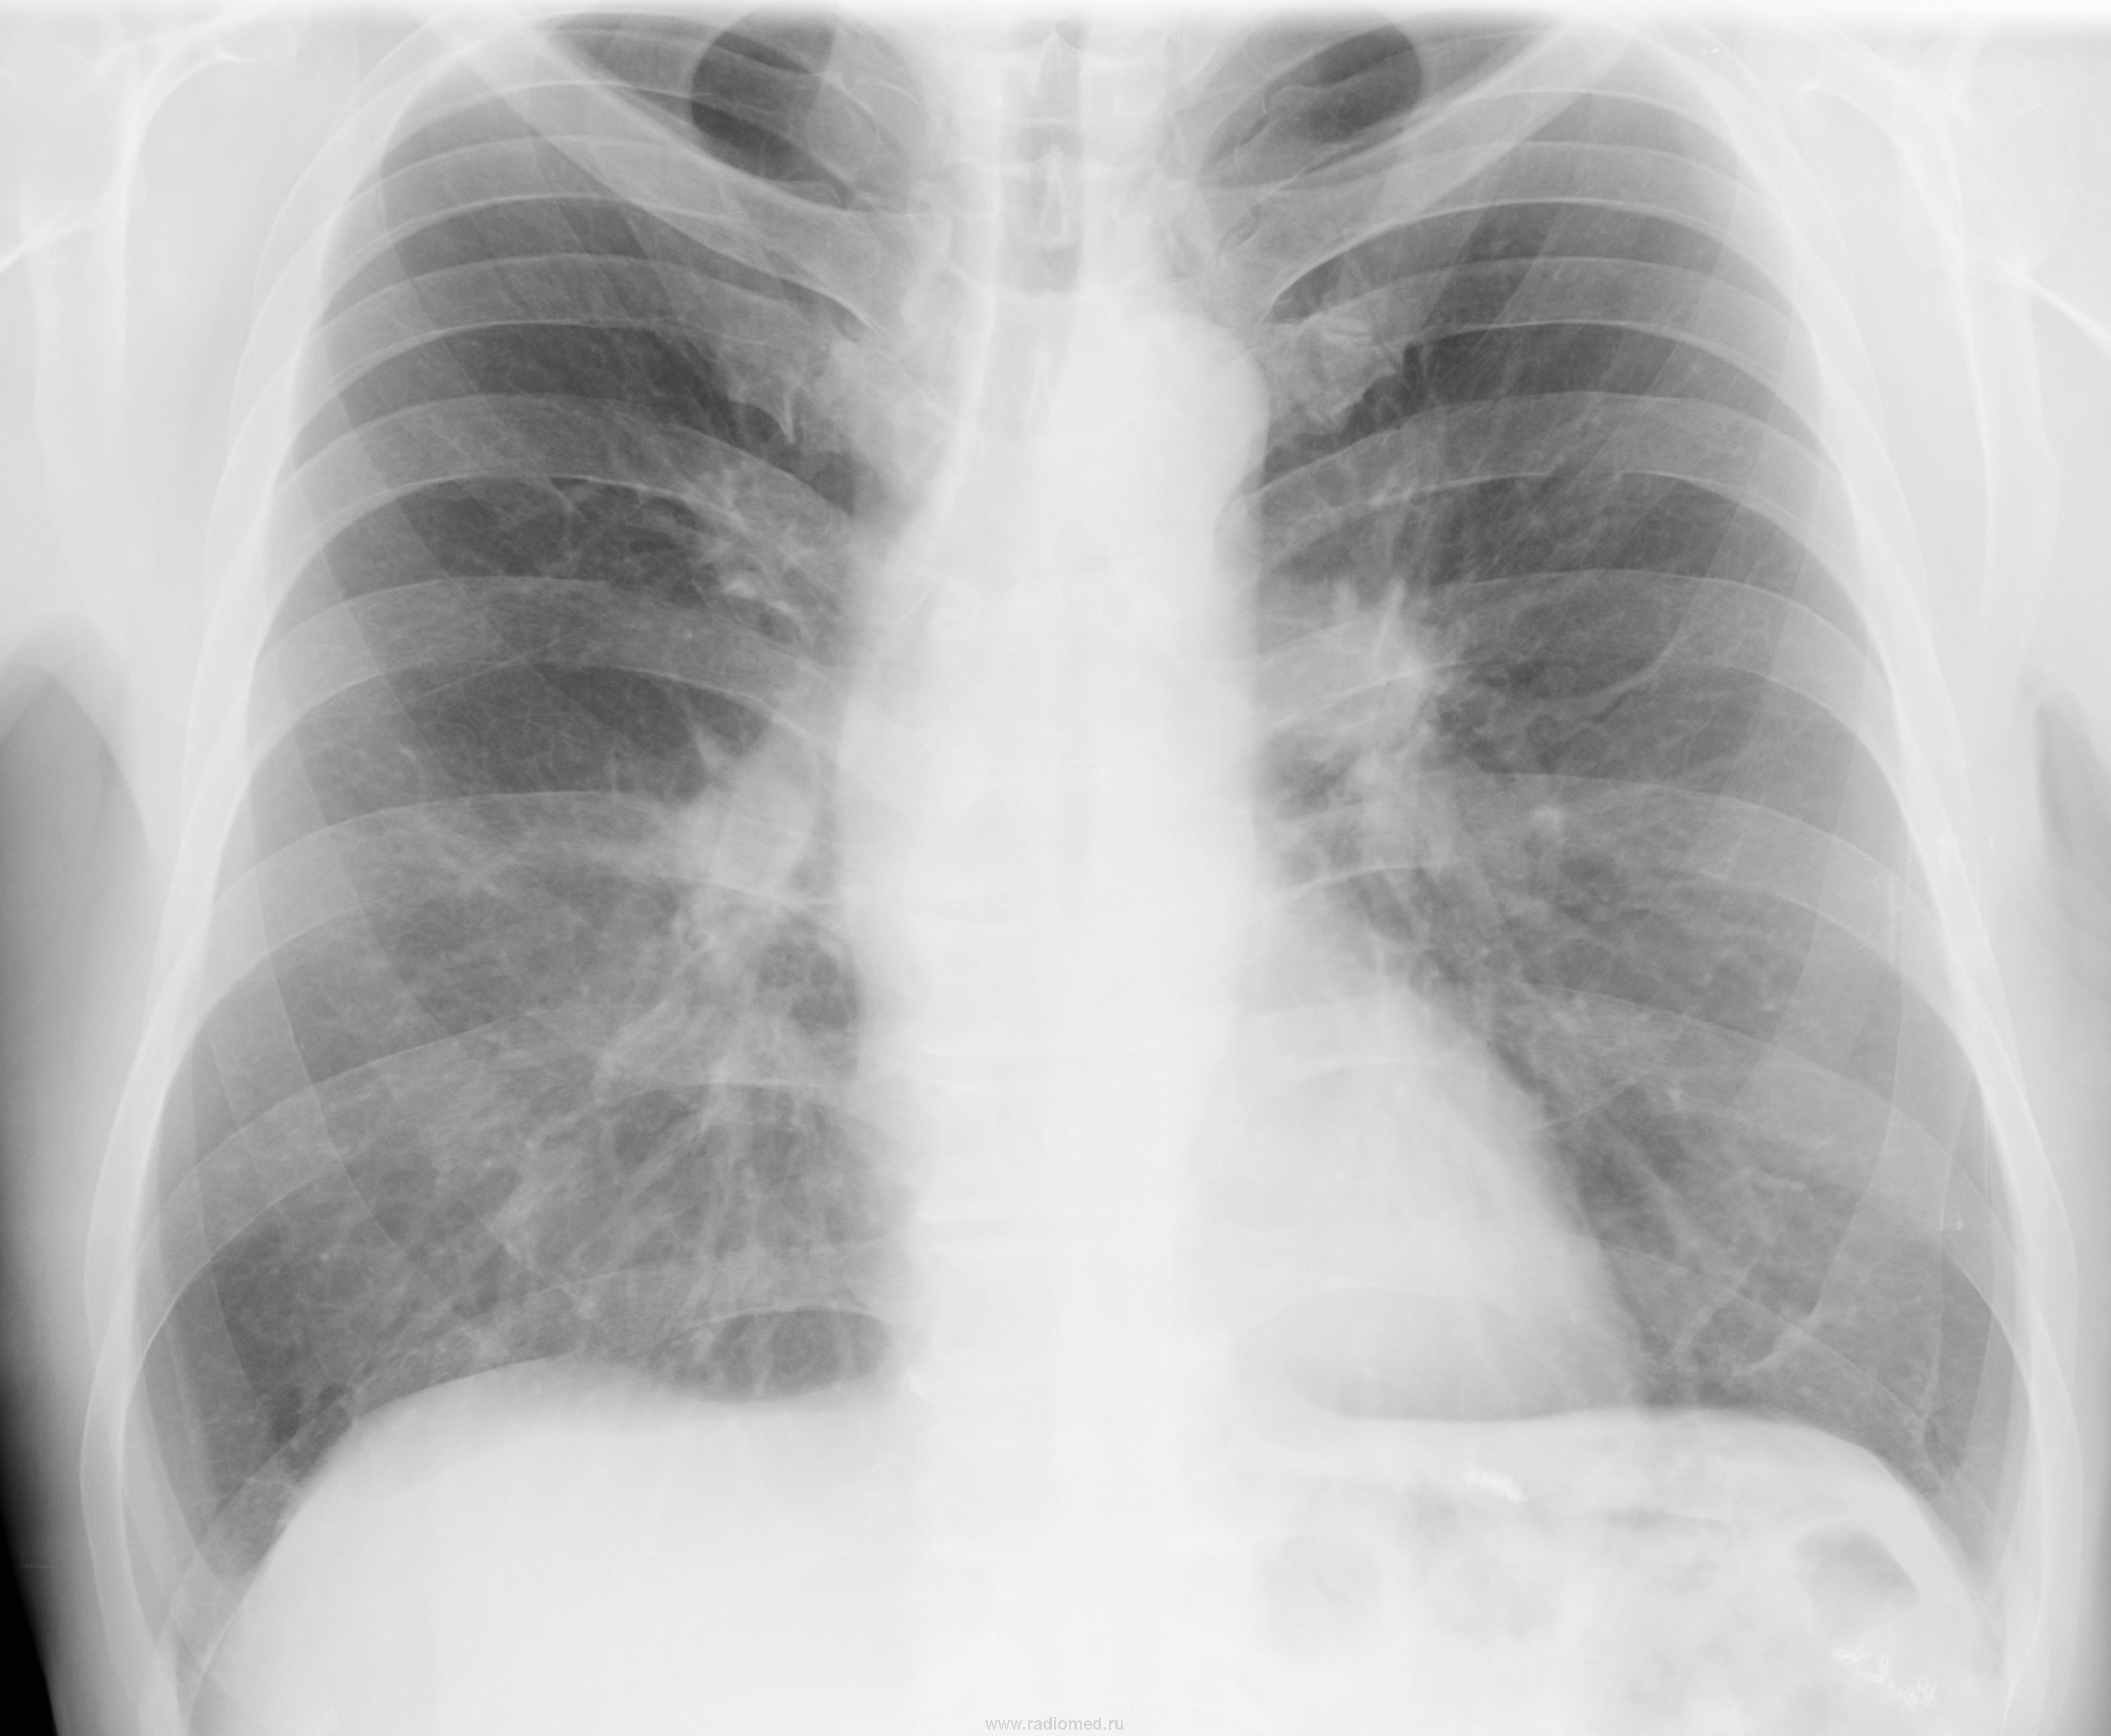

Смещение средостения вправо, трахея стянута в бок, признаков ателектаза не видно(вроде),небольшое затемнение в правом 2 межреберье, необходима консультация онколога.(Cr-?)

kintire можно аплодировать. В теле позвонка Th8 деструкция с отеком. Оперирован по поводу рака желудка IIIст.

и все же очаг убыли костной ткани 2см виден хорошо ;)

А c телами Тh6, Th7 все хорошо?

Объемное образование на уровне бифуркации трахеи.